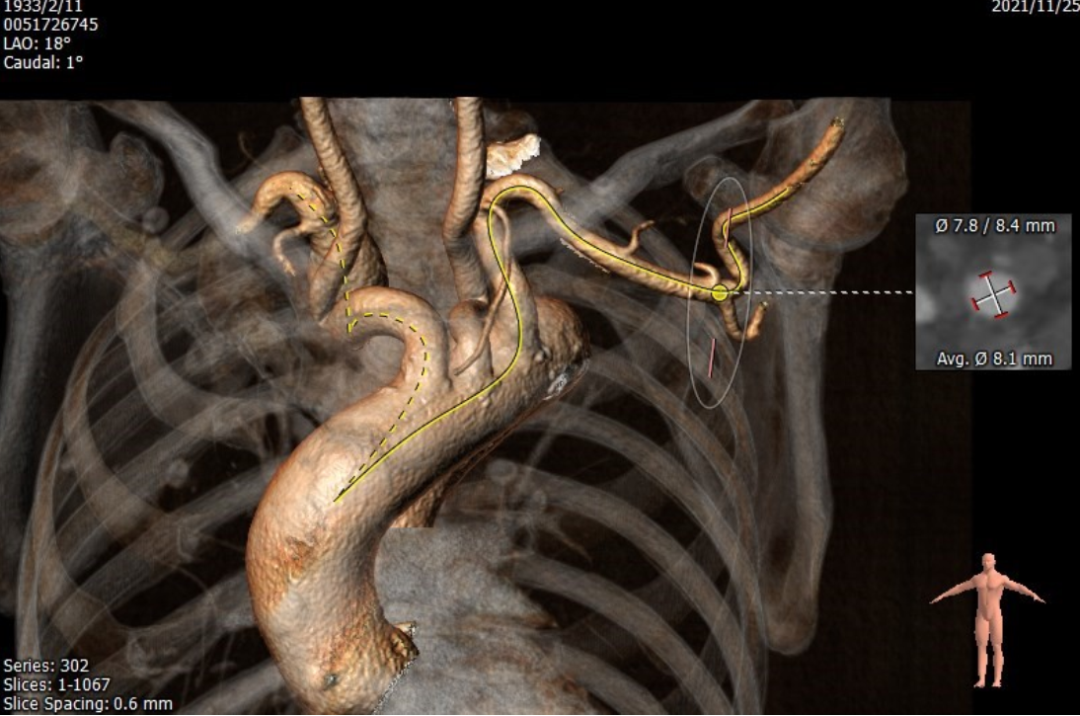

该病例特点为:该患者考虑为心脏联合瓣膜病导致心力衰竭,并且药物治疗效果差,有瓣膜手术的指征。患者88岁高龄,BMI 17.3Kg/m2,营养状况差,合并肾功能不全,STS评分20.848%,外科手术风险极大,考虑患者心脏瓣膜疾病以主动脉瓣为主,二尖瓣及三尖瓣关闭不全为继发性改变,建议首先行TAVR治疗。该患者行TAVR治疗需要面临以下几个方面的问题:1、TAVR术中应用造影剂会导致患者肾功能恶化,由于患者心功能差,术前水化很有可能会加重心衰。2、患者股动脉、髂动脉扭曲,特别是主动脉极度迂曲,经股动脉入路可能出现器械通过困难,或者器械被血管夹持的情况。该患者双侧颈动脉及右侧锁骨下动脉扭曲严重,左侧腋动脉是可选择入路,但是可能面临缝合效果欠佳无法压迫止血,外科切开止血的情况。3、患者为三叶瓣,无钙化,瓣叶对人工瓣膜的锚定力不足,给术中瓣膜定位、释放带来了很大挑战,另外有术后瓣膜移位的风险。4、该患者主动脉瓣病变以反流为主,选择人工瓣膜型号oversize要偏大,导致房室传导阻滞发生率高,需要延长留置临时起搏电极的时间,但是患者三尖瓣重度关闭不全,很有可能导致临时起搏电极脱位,导致灾难性的后果;另外,长时间留置临时起搏电极,导致患者行动不便,增加了卧床相关并发症的发生率。

心脏瓣膜病介入中心联合心外科、血管外科、麻醉科、体外循环、手术室、肾内科等兄弟科室,制定了详细的治疗计划:在密切关注心功能的情况下予患者水化治疗、术中尽可能的减少造影剂的用量,以降低肾功能损害。首先尝试以右侧股动脉为主入路,应用65cm的鞘管(GORE DRYSEAL FLEX)进行。左侧腋动脉途径做为备选方案,同时准备外周球囊、覆膜支架等器械。结合患者主动脉根部及瓣叶解剖特点,选择vitaflow 可回收瓣膜系统进行TAVR治疗。针对可能出现的房室传导阻滞及临时起搏电极位置不牢靠的问题,考虑在必要的情况下应用半永久起搏器技术,以达到满意的起搏效果、有利于患者术后康复,同时可以监测患者心律,避免不必要的永久起搏器植入。

3、 该患者经下肢入路血管严重扭曲,65cm的GORE DRYSEAL FLEX鞘管为此类患者提供了解决之道。

4、 为获得良好的输送效果,鞘管头端已经跨越过主动脉弓部至升主动脉,在此过程中需要特别谨慎操作,而且为了减少导丝对动脉壁的损伤,未选用Lunderquist导丝,而是选用相对较软的Super stiff导丝。